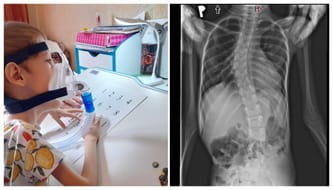

Wiktor jest już dużym chłopcem. Ma 8 lat i wie, że jego mięśnie są bardzo chore i to przez ich zanik jest zależny od innych. Pomimo to nie boi się marzyć, nie boi się wyzwań, a jego wiara w to, że będzie zdrowy jest wprost niesamowita.

Dlatego z jego dziecięcą wiarą i wdzięcznością sam osobiście chciałby powiedzieć Wam "dziękuję". Nasz syn wie, że każda wpłata, która była przekazana na jego zbiórkę to nie tylko pieniądze, ale przede wszystkim potężne narzędzie do walki z jego chorobą. Wiktor należy do tych osób, które nigdy się nie poddają. Jest uparty i dąży do celu. Jego cel to zdrowie, samodzielność, niezależność i kiedyś... praca w laboratorium. Jego upór i wiara nie wzięły się znikąd. Nasz syn widział dzieci , które powróciły do zdrowia po podaniu leku w ramach badań i jego dziecięca wiara pozwala mu budować obraz jego przyszłości w pięknych kolorach. Nie ma w nich miejsca na chorobę i dlatego jest niesamowicie zmotywowany do walki o każdy dzień, który przybliży go do celu.